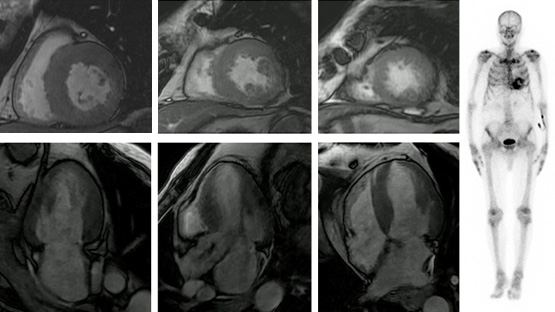

- ETT : sérites (épanchements pleuraux bilatéraux bilatéraux de moyenne abondance, épanchement péricardique circonférentiel non menaçant), atteinte pancardiaque (hypertrophie ventriculaire gauche et droite, épaississement des feuillets valvulaires). Aspect du GLS en cocarde (ou « œil de bœuf ») très évocateur.

À l’échographie cardiaque (cardiopathie amyloïde ; non spécifique de l’amylose AL) :

- Atteinte pancardiaque (hypertrophie ventriculaire gauche, ventricule droit, feuillets valvulaires)

- Sérites (plèvres, péricarde).

- Global longitudinal strain avec un gradient base-apex dessinant une cocarde ou « œil de boeuf » (aspect très évocateur, mais non spécifique de l’amylose)